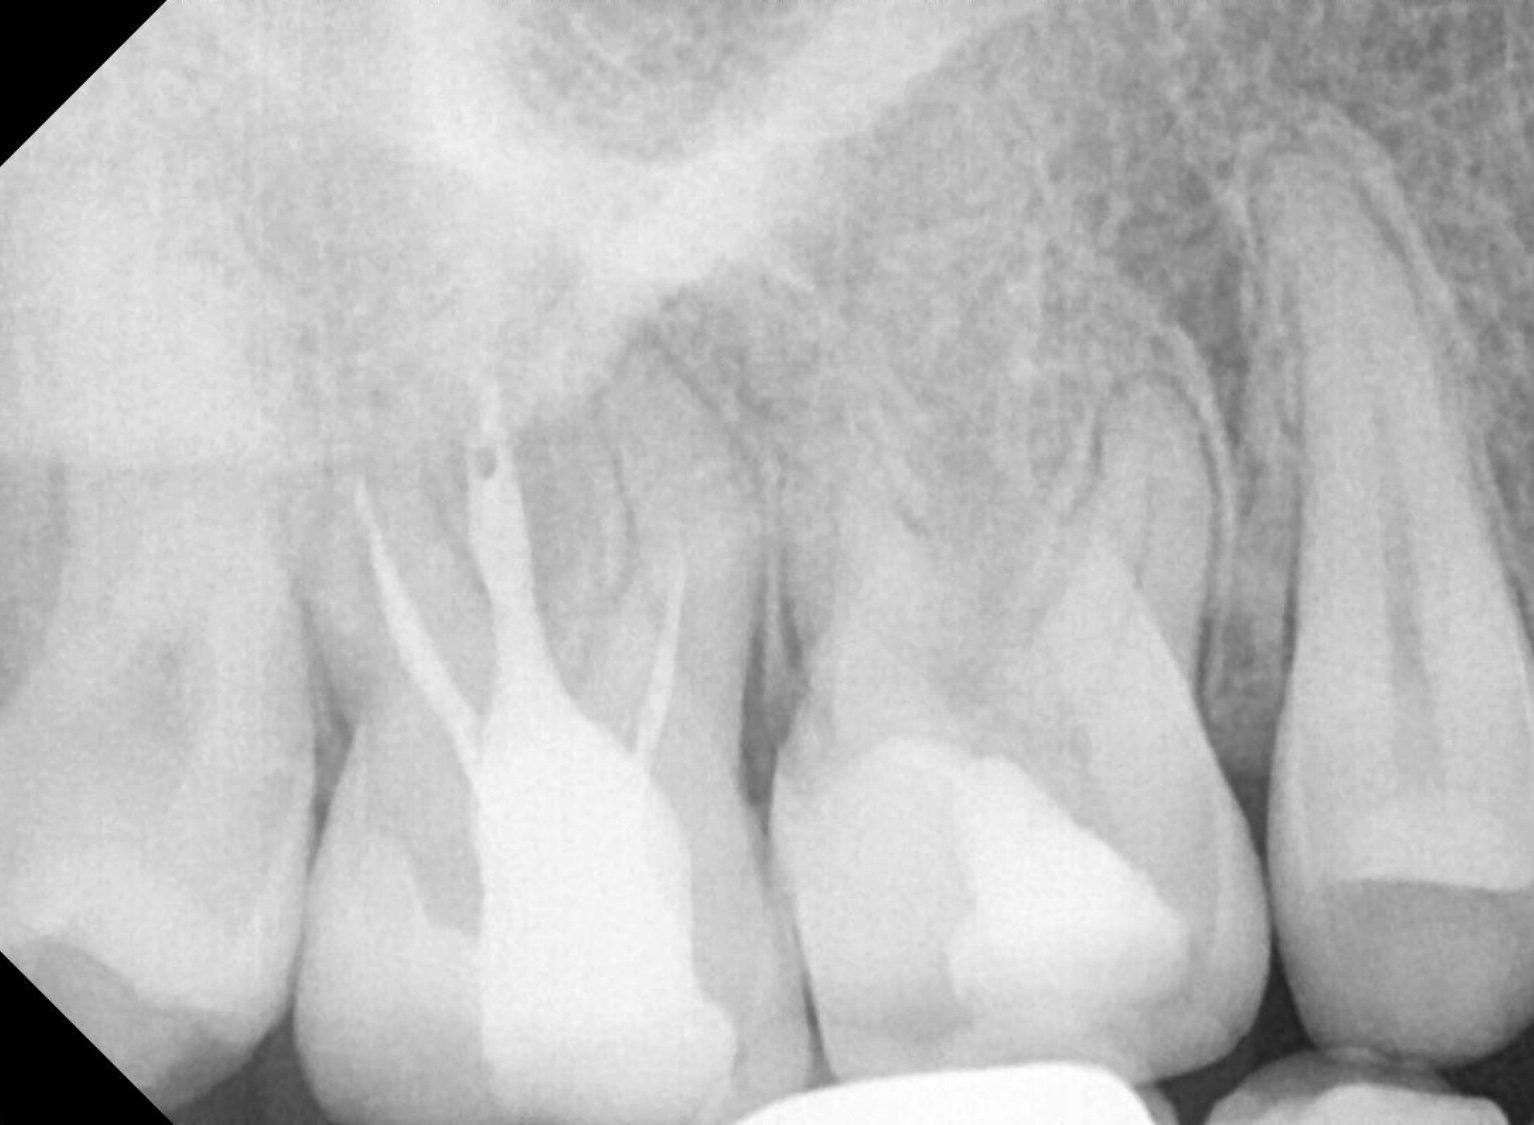

Лечението на хроничен периодонтит на млечни зъби включва премахване на инфекцията и възстановяване на здравето на зъбите. Обикновено се извършва кореново канално лечение, което включва почистване на кореновия канал и запълване със специални материали. При наличие на фистули и гноене може да се наложи и антибиотична терапия. В случай на продължаващи проблеми, консултацията с орален и лицево-челюстен хирург или ортодонт може да бъде от полза.

Ако пълнежът излезе извън коренови канал, това може да създаде проблеми. Излизането на пълнежа може да доведе до инфекция или реинфекция на зъба. В такъв случай е необходимо да се консултирате със зъболекар, който може да прецени дали е необходимо повторно лечение на кореновите канали или други процедури за спасяване на зъба.